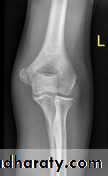

Failure to diagnose these injuries can lead to significant long term disability. Fortunately as these injuries involve an apophysis rather than an epiphysis, no growth arrest of the arm occurs, however elbow instability and even recurrent dislocations can result from suboptimal healing.Fifty percent of medial epicondyle fractures are associated with an elbow dislocation.

It is important to distinguish a medial epicondyle fracture (common) from a medial condyle fracture (very rare). Medial condyle fractures are intraarticular, extending into the elbow joint and require urgent open reduction internal fixation (ORIF).